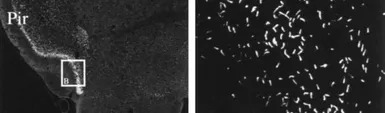

IHC-P analysis of rat brain tissue using GTX79169 Somatostatin receptor 3 antibody.